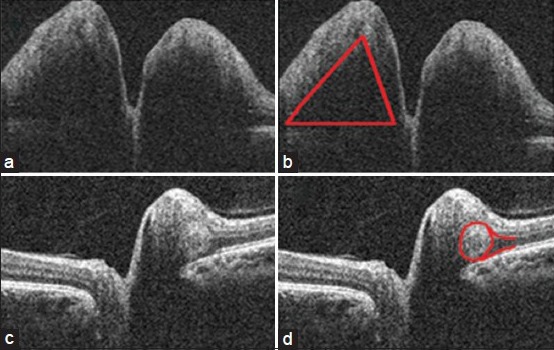

Figure 2.

Buried optic nerve head drusen seen as a round hyperreflective echo (red arrow) above the retinal pigment epithelium

In pediatric patients with papilledema, an objective method of evaluation of disc swelling while monitoring the treatment is an easy option. El-Dairi et al. have shown the feasibility and accuracy of the same in pediatric age group.[12] Rebolleda and Muñoz-Negrete have quantitatively correlated RNFL thickness with visual field sensitivity losses.[13] They showed that for every 10 μm of mean RNFL thickness increase at baseline, there was a 0.6-dB decrease in mean deviation at the last follow-up. The main problem using OCT to observe patients with papilledema, is there is no way, based on OCT alone, to determine, when RNFL thickness returns toward normal, whether it implies patients are improving or that they are actually losing nerve fibers. A discrepancy between OCT and visual field testing can be helpful. Hence, serial OCT imaging and perimetry can be the standard in monitoring papilledema. Since all our patients showed a decrease in papilledema after initiation of treatment, the serial OCT showed a decrease in the RNFL thickness in all the patients [Fig. 3]. We also noticed discrete hyper reflective echoes above the RPE in patients with resolving papilledema at the level of the watermark sign seen in regressing disc swellings [Fig. 4]. OCT can definitely be used as a tool to monitor the treatment in IIH.

In resolving papilledema at the level of the watermark sign a discrete hyperreflective echo seen above the retinal pigment epithelium